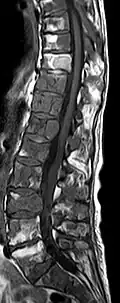

Sagittale native T1-gewichtete MRT -

Sagittale native T1-gewichtete MRT. Deutlich sichtbar die Ausdehnung bis in die Bogenwurzeln.